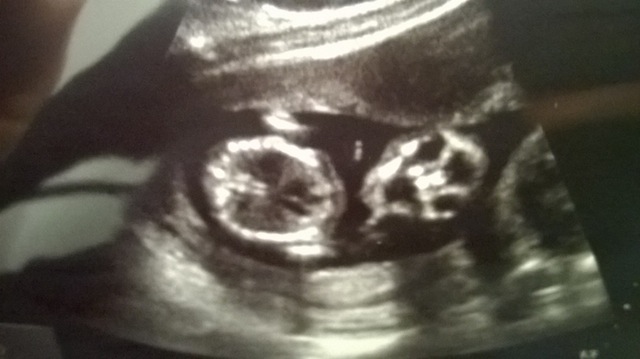

However, if you look at the 3rd pic below where the baby's mouth is wide open screaming "leave me alone", it has its legs up on the air on both sides and you can kinda see a long fork-shaped thing in the middle. I know its difficult to tell from this crazy angle but maybe someone who has a boy/girl will recognize something? Or maybe someone could comment on the skull shape perhaps?

Attachment 18699